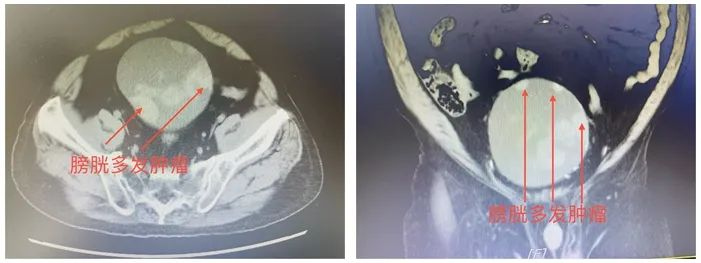

患者入院后CT提示:膀胱壁多发结节,考虑膀胱恶性肿瘤。进一步完善血常规、肺通气功能、血气分析提示患者重度贫血、极重度混合性通气功能障碍、Ⅱ型呼吸衰竭。患者入院后留置尿管并持续膀胱冲洗仍不能解决血尿及腹部疼痛问题,患者及家属寄希望能够进行手术,一次性解决膀胱癌问题。

▲患者术前泌尿系造影CTU结果